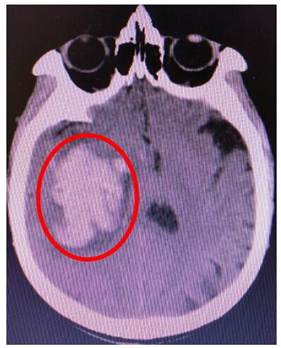

来自长寿区的魏大爷是一位高血压患者,因平时没有头晕头痛等任何高血压症状,未引起重视,也没有长期监测并控制血压。突然有一天,他在过度劳累后突发左侧肢体无力,说话不清,意识障碍。子女将他送往我院行头部CT,CT明确右侧基底节区出血,这是高血压脑出血最常见的部位。

我院神经外科陈晋副主任医师和黄宁医师根据CT结果进一步估算,出血量约45ml,脑组织受压明显,需立即手术挽救生命。

手术历经2小时,术后患者意识清醒,复查头部CT示术中将大部分血肿清除,一周后拆线出院。